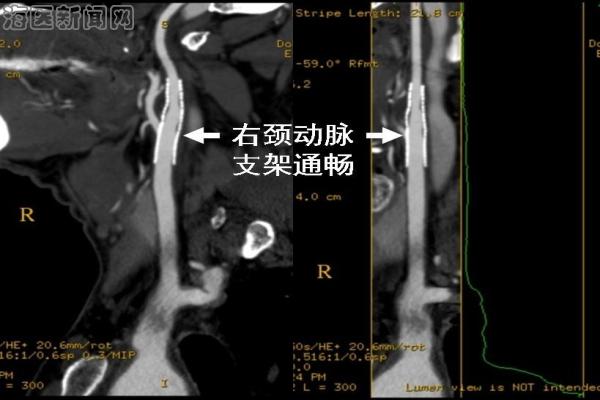

病例2 张某某,男,63岁,突发左侧肢体瘫痪入院,既往有吸烟和高血压病史,MRI检查发现右侧大面积脑梗死,全脑血管造影(DSA)发现右侧颈内动脉重度狭窄,脑供血明显不足,患者同意后在局麻下行颈动脉支架置入术,术后即刻造影显示颈动脉狭窄解除,血流恢复通畅,脑供血不足明显改善。患者术后瘫痪症状明显改善,第4天出院。术后随访1年8月,CT血管造影(CTA)显示支架通畅,患者独立行走。

术后1年8月,患者复查CTA,颈动脉支架通畅,患者能够独立行走。